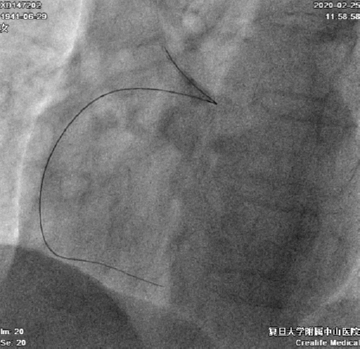

在135cm Corsair微导管支撑下0.014’’Sion送至RCA中段闭塞处,换入Fielder XTR导丝很快通过闭塞段,送至右冠远端。(图5)

图5